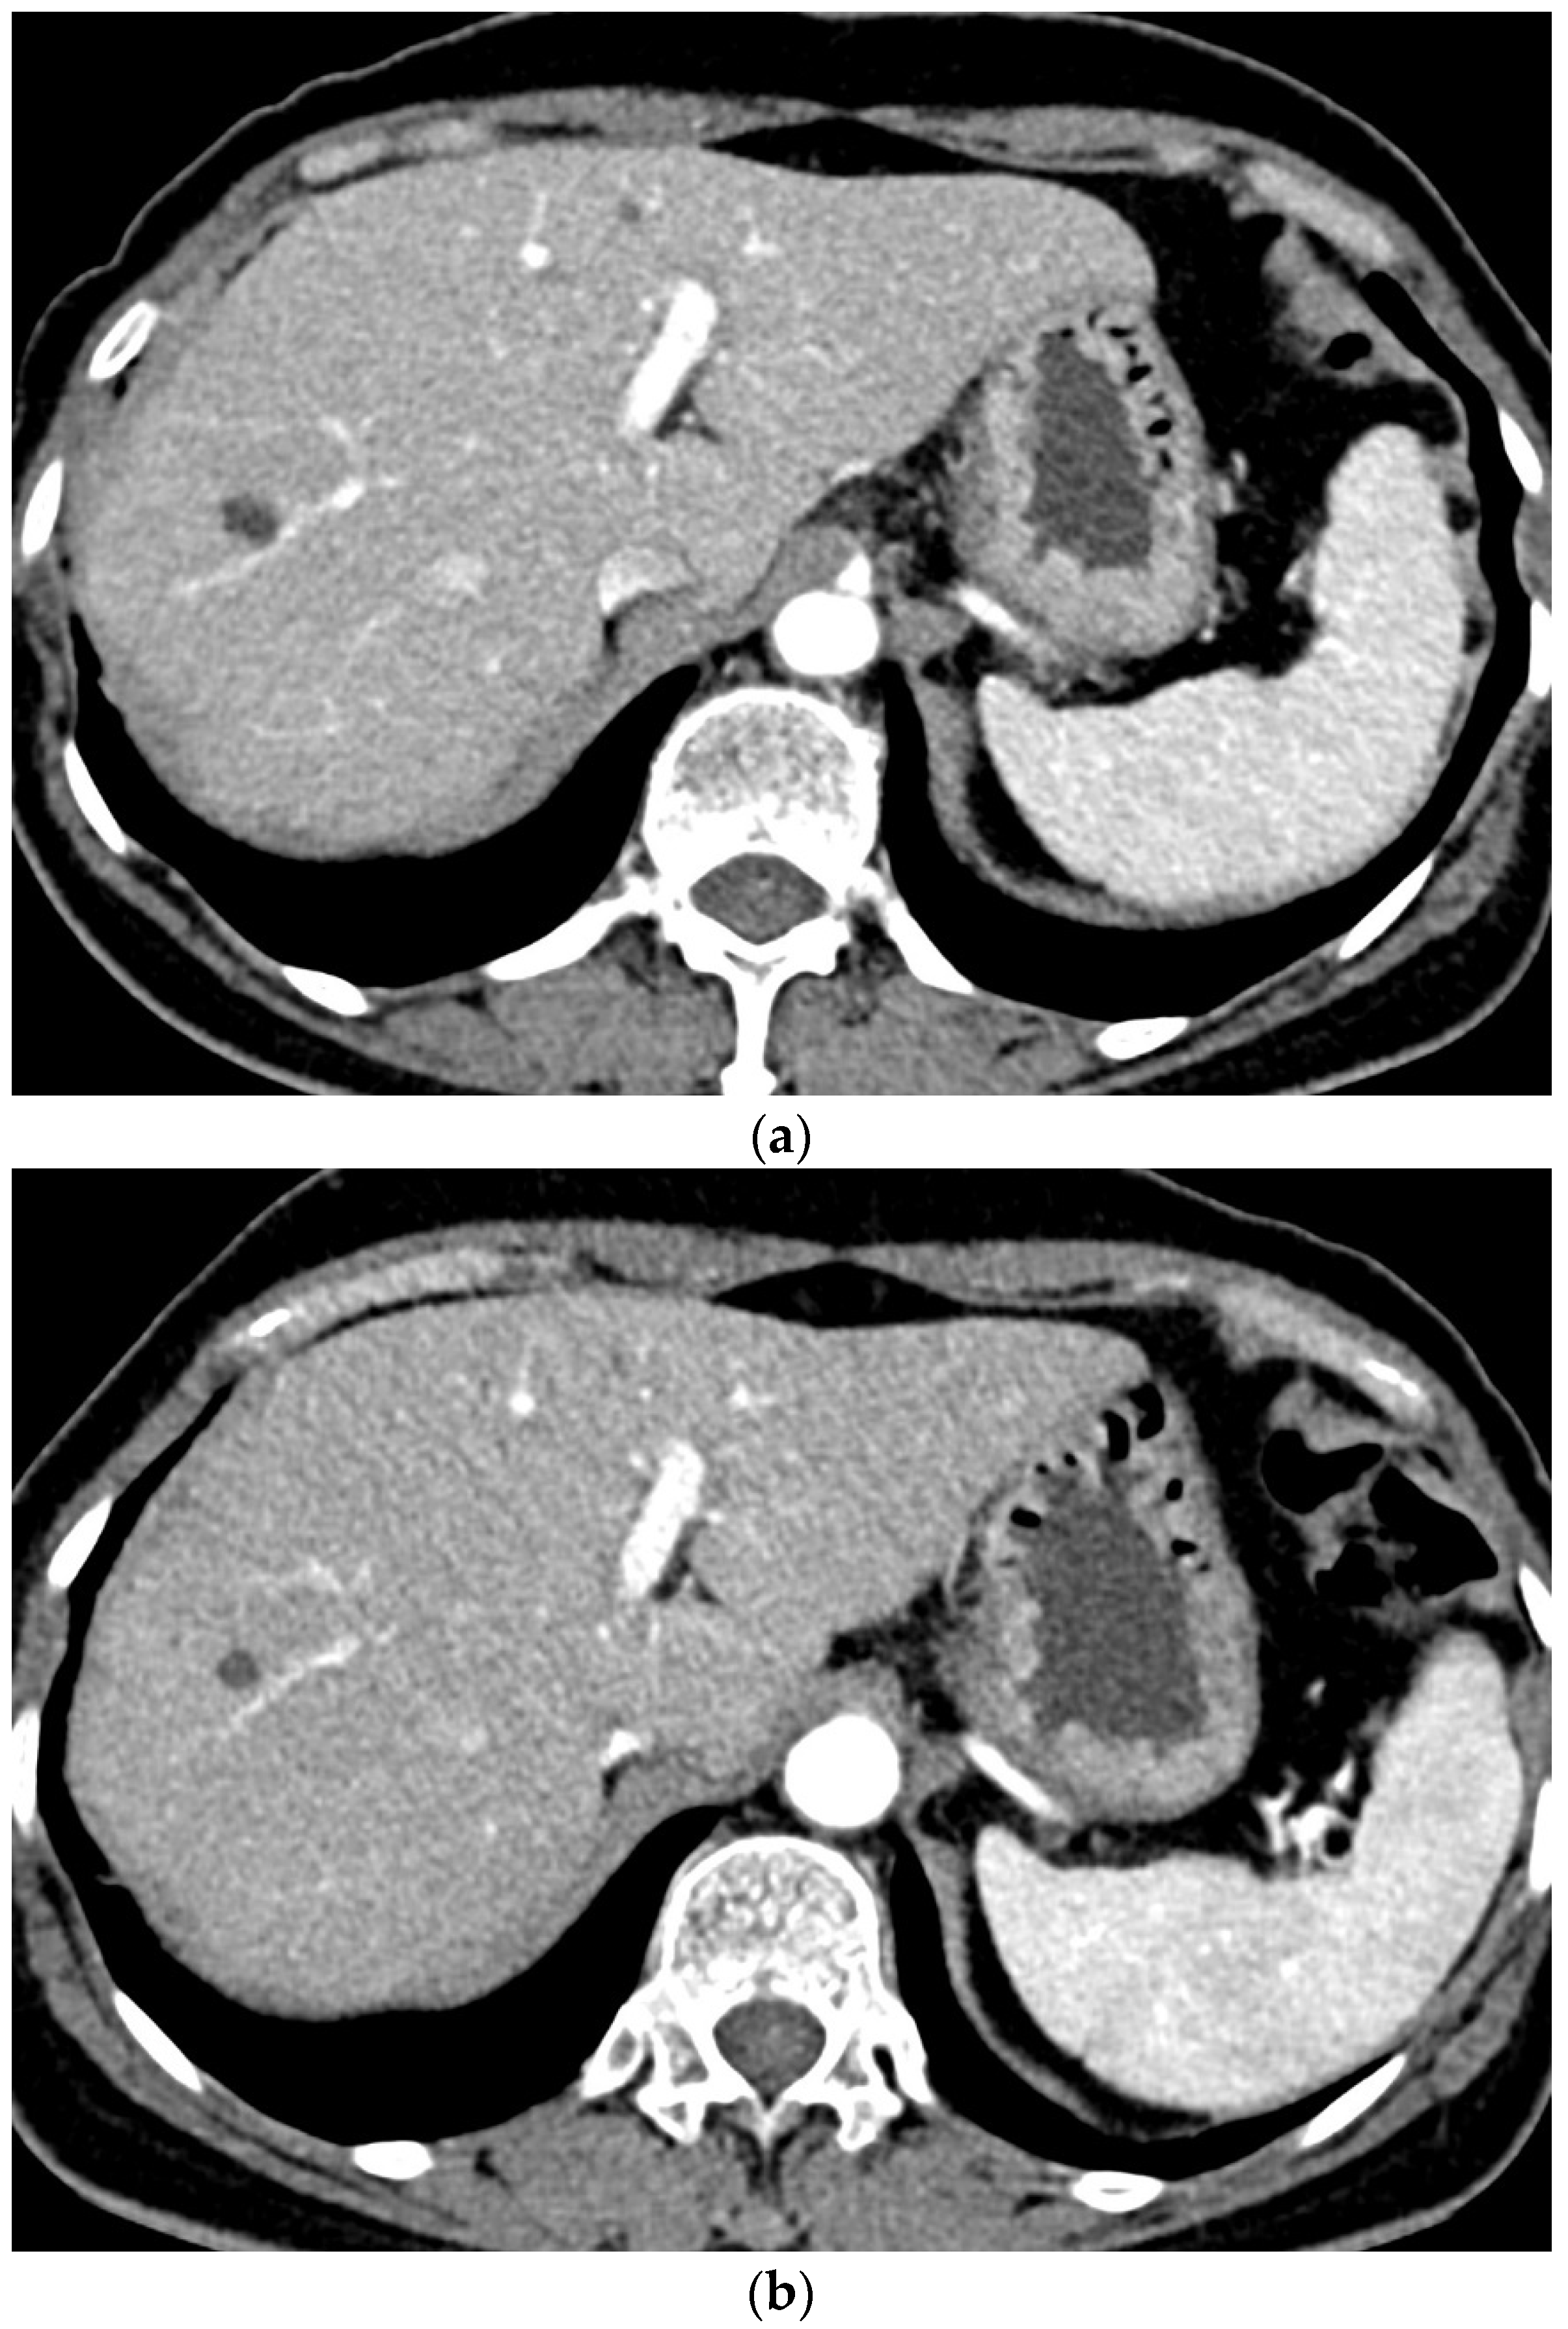

Two radiologists with more than 10 years of experience with abdominal radiology independently evaluated the chest CT images that were reconstructed with soft kernel (Br40). For quantitative analysis, they identified seven regions of interest (ROIs) in the liver, pancreas, spleen, kidney, aorta, portal vein, and paraspinal muscle. It was recommended that the size of the ROI be 2 cm2 or larger in the liver, spleen, and paraspinal muscle and as large as possible in the other organs on the single axial image that contained the largest area of each organ (Figure 1). They drew ROIs in the renal cortex avoiding the medulla to evaluate the kidney and in the paraspinal muscle area that showed the most homogeneous density. From the ROI, the mean density and standard deviation (aka noise) were extracted. The signal-to-noise ratio (SNR) was calculated as the mean density/standard deviation in each organ. The contrast-to-noise ratio (CNR) relative to muscle was calculated as (mean density of the organ–mean density of the paraspinal muscle)/standard deviation of the paraspinal muscle.

Figure 1. Quantitative analysis of the CT images A radiologist draws multiple regions of interest in the liver, pancreas, spleen, portal vein, and aorta (a) and in the kidney and paraspinal muscle (b).